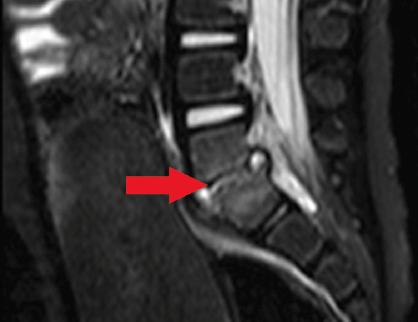

discitis

David Effron, MD; Maya C. Myslenski, MD

A 25-month-old white female presented with a 1.5-week history of intermittent, cramping, diffuse abdominal pain, increasing irritability, and decreased activity.